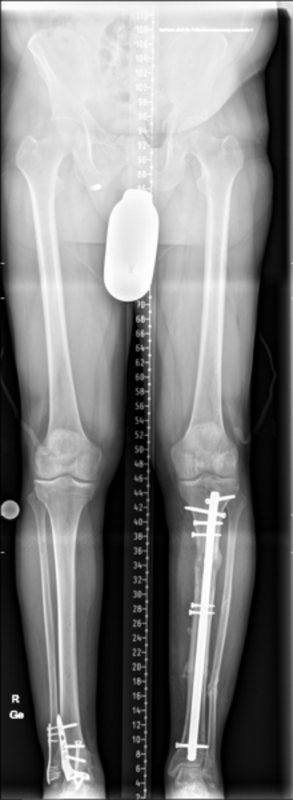

Von der Fraktur über die Pseudarthrose zum Segmenttransport

Vorgeschichte: Herr M. zog sich vor drei Jahren im Rahmen eines BG-lich versicherten Motorradunfalls eine I°ig offene mehrfragmentäre Tibiaquerfraktur mit 2-Etagen-Fraktur der Fibula links sowie eine OSG-Luxationsfraktur rechts zu.

Die initiale Versorgung erfolgte in einer Klinik der Maximalversorgung mit Fixateur extern Anlage und Transfixation des Sprunggelenks. Im Verlauf erfolgte der Verfahrenswechsel auf einen Tibia-Nagel links und Fibulaplatte mit Zuggurtung des Innenknöchels rechts.

Vorstellung in einem Zentrum: Ein Jahr nach dem Unfall erfolgte bei persistierenden Schmerzen die erstmalige Vorstellung in einer BG-Klinik. Hier zeigte sich eine Subluxationsstellung der Sprunggelenksfraktur auf der rechten Seite mit weit fortgeschrittener posttraumatischer Arthrose. Auf der linken Seite zeigte sich eine befriedigende Stellung bei noch erheblicher Defektzone lateralseits und nicht ganz aufeinander stehenden Frakturenden aber in regelrechter Position. Es erfolgte zunächst die Sprunggelenksarthrodese rechts um eine stabile, schmerzfreie Seite zu erhalten.

Rekonstruktion: Bei Infektverlauf mit Nachweis von Staphylococcus aureus und Staphylococcus epidermidis sowie histologischem Nachweis einer chronischen Osteomyelitis an der linken Tibia erfolgte 1,5 Jahre nach dem Unfall die Infektsanierung mit Segmentresektion und anschließend der Segmenttransport mittels Precice-Bone-Transport-Nail.

Nach etwa 2 Monaten konnte das Kompressionsdocking erfolgen. Bei weitgehender Konsolidierung über ein Jahr nach der Implantation erfolgte die Metallentfernung des einliegenden Segmenttransport-Nagels sowie die Anpassung eines Braces zur weiteren Ausbehandlung.

Resümee: Erst durch die konsequente Segementresektion konnte der Infekt eradiziert werden. Durch die Therapie mit dem noch relativ neuen Verfahren des Segmenttransportnagels konnte dem Patienten die zwar ebenfalls meist erfolgreiche, jedoch deutlich belastendere Therapie mit einem Ringfixateur erspart werden.